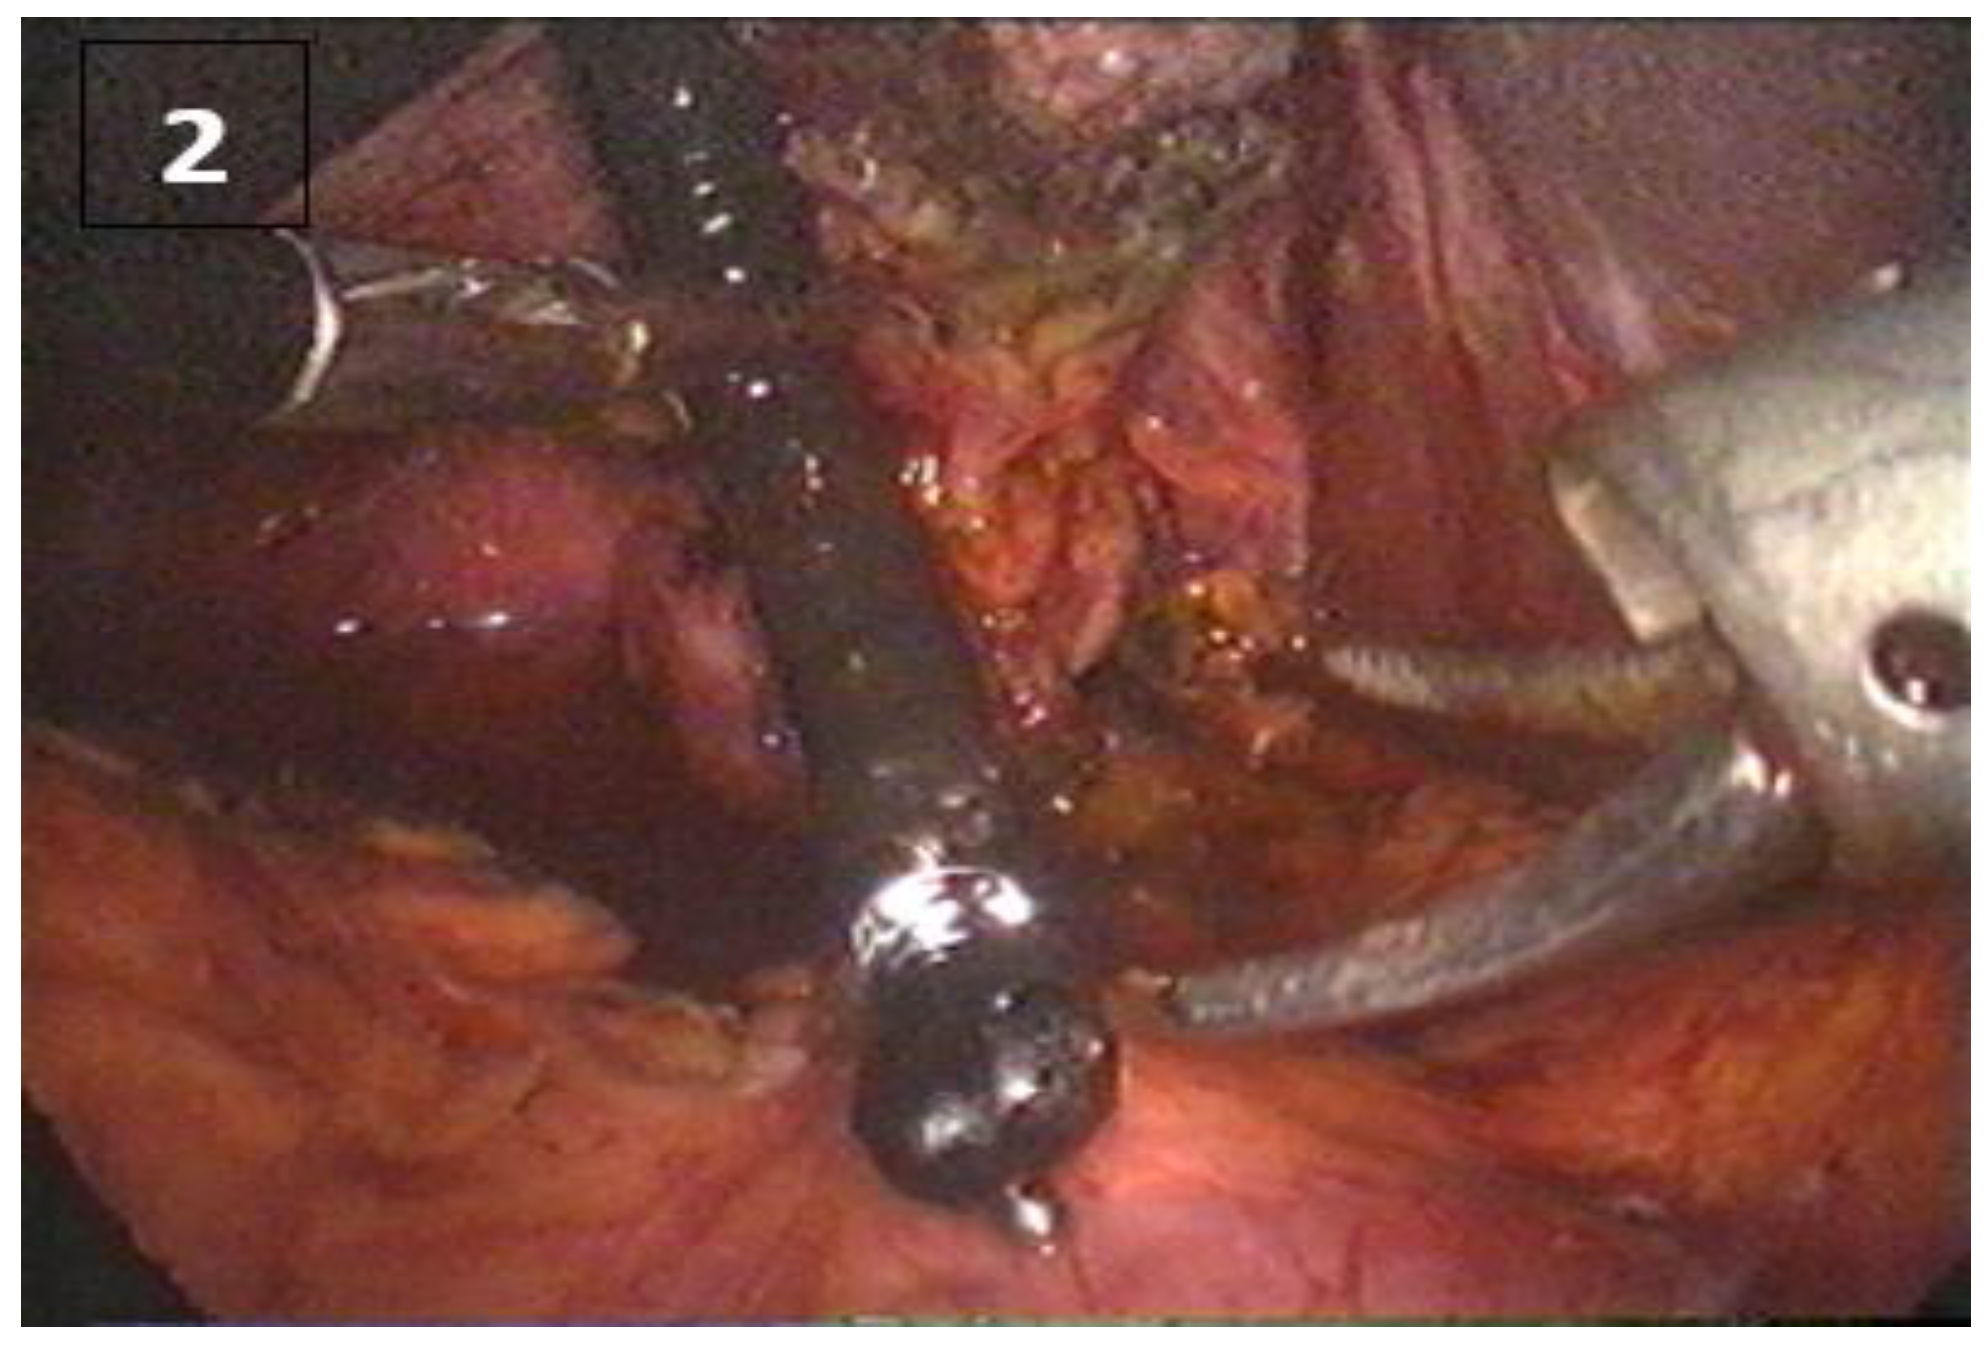

A small transverse breach will be created in the cystic duct, through which a cannula is inserted to perform the laparoscopic cholagioscopy (Figure 1). The cholangio-fibroscope is inserted through cannula no. 3 (located on the midclavicular line below the rib margin) in the abdomen and will be guided into the cystic duct by means of an atraumatic clamp (Figure 2). If the cystic duct is not wide enough, it will be dilated using a catheter equipped with a balloon which has a diameter of 5-7 mm (cholangio-fibroscope has a diameter of 3-5 mm) (Figure 2). During this time, the operator must simultaneously observe the information provided by the two monitors: the laparoscope and the cholangiofibroscope. If the local anatomy also allows and the cystic duct is short and perpendicular to the common hepatic bile duct, the operator can use the fiberscope to ascend to the level of the intrahepatic branches of order 2 even 3. The investigation will be concluded either by the external drainage of the cystic duct that serves to extract any residual gallstones or by its ligation/clipping. For an experienced surgical team, the exploration does not exceed 15 min.

Figure 1. Main bile duct stone extracted through a transcystic approach (part 1).

Figure 2. Main bile duct stone extracted through a transcystic approach (part 2).